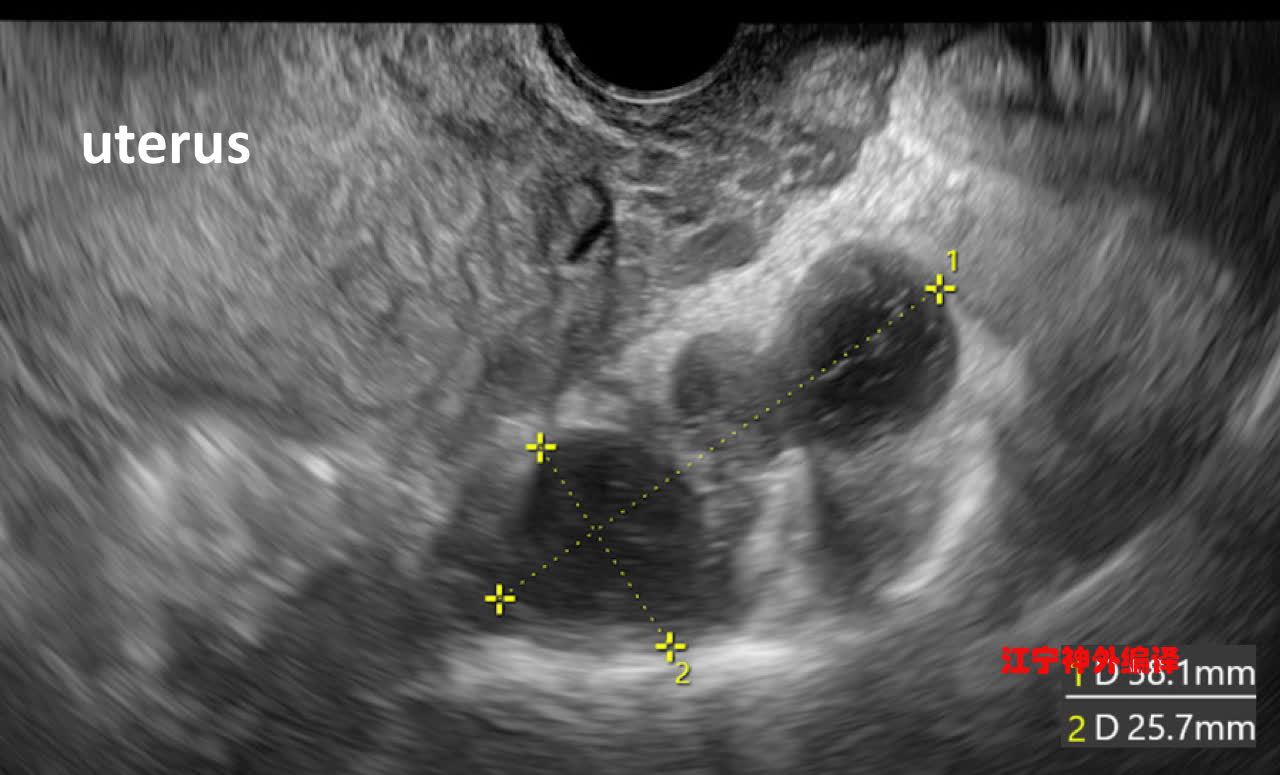

42岁孕妇,妊娠23周,盆腔磁共振诊断为巨大的双侧骶前囊肿,从骶孔向两侧延伸至盆腔,最大径超过6厘米。同时观察到骶管轻微扩大。

妊娠 34 周的磁共振影像:骶前囊肿在中线右侧与胎儿头部相邻。

日本学者回顾文献发现,巨大骶前囊肿如果被切开、或者在分娩过程中自动破裂,会导致严重的低颅压性头痛、骶丛神经痛加剧,因此应避免骶前囊肿破裂。向囊肿内注射酒精会导致非常严重的后果,包括马尾综合症,应禁止。根据文献,对于这类患者,阴道分娩和剖宫产都是可以的。本例患者最终选择了全麻下剖宫产,产后6天B超检查,显示骶前囊肿没有破裂,也没有出现新的症状。